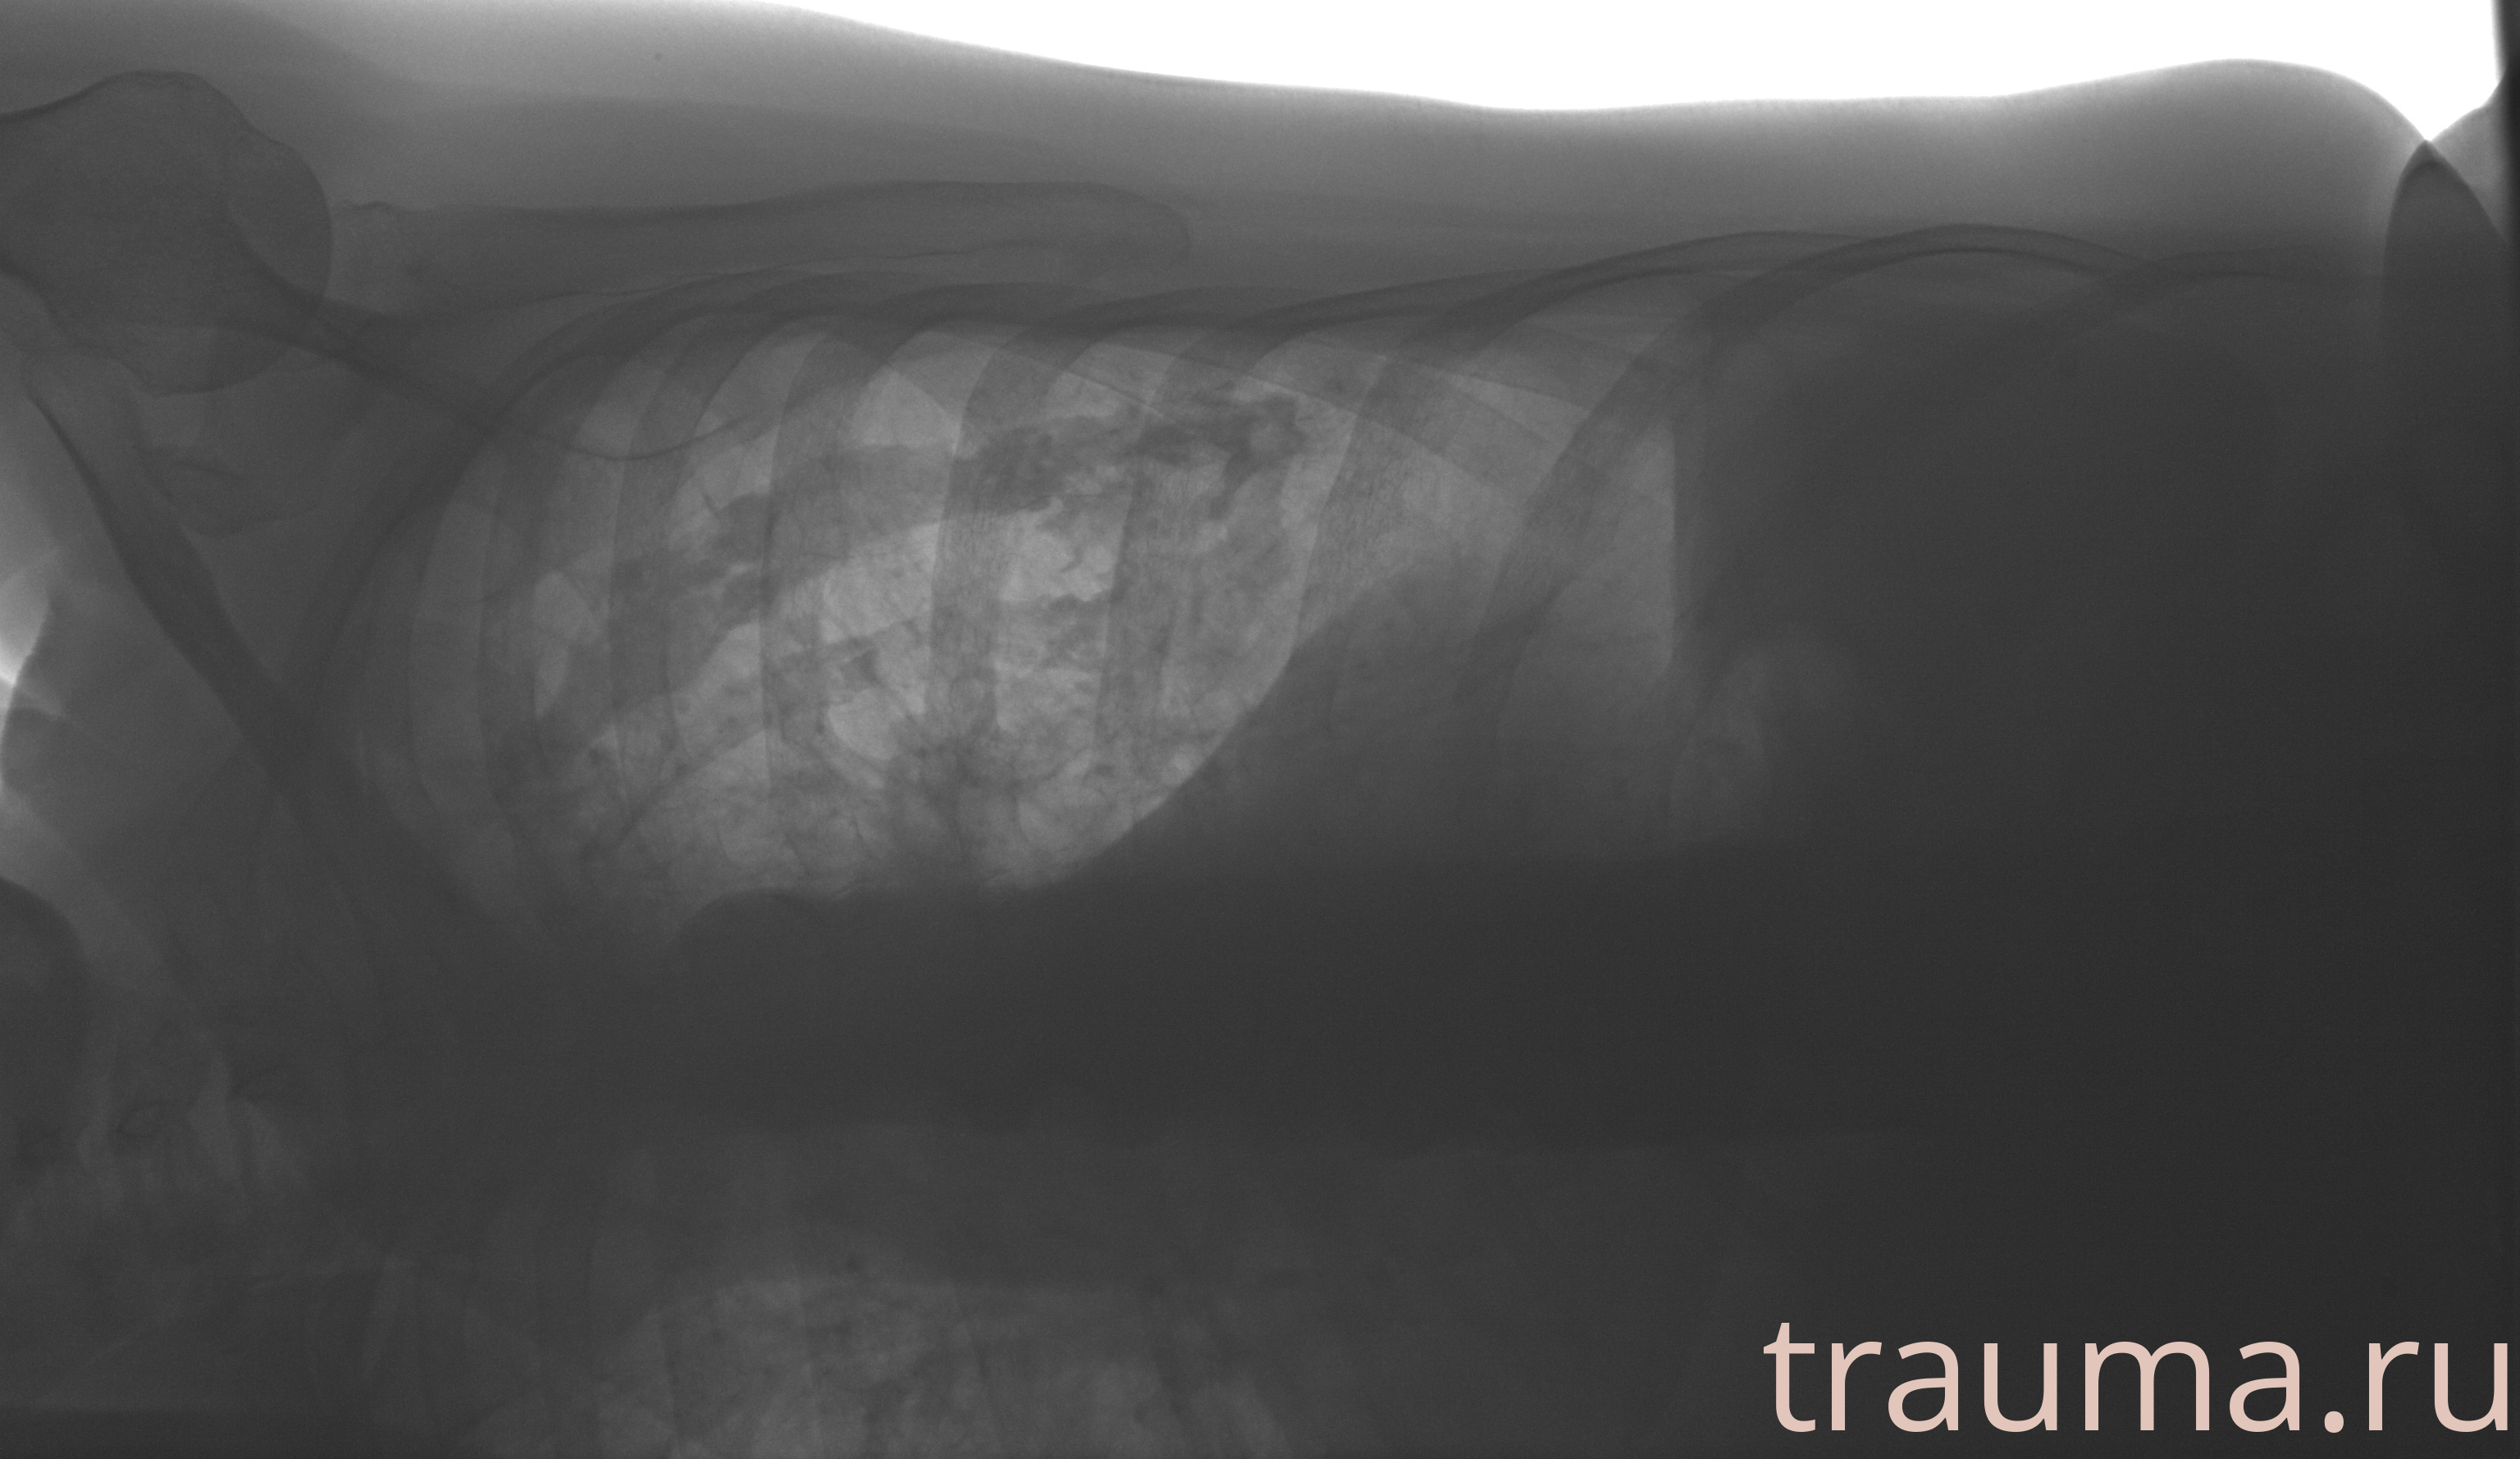

Рентгенограммы

Рентген на дому: по вашему адресу приезжает врач-рентгенолог, травматолог-ортопед с мобильным рентгеновским аппаратом, проводит диагностику травмы или заболевания, делает необходимые рентгенограммы, дает рекомендации по дальнейшему лечению. Получить качественные снимки в домашних условиях возможно благодаря уникальной методике, разработанной МосРентген Центром для института  Склифосовского

при переломе шейки бедра и пневмонии от компании МосРентген Центр - партнера Института имени Склифосовского